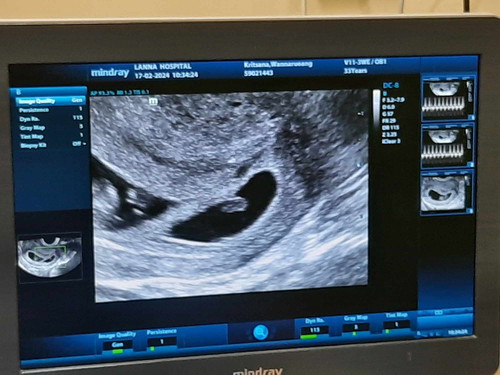

ฝากครรภ์ครั้งแรก แฝด แต่... อาจได้ไปต่อแค่ หนึ่ง

8w คนหนึ่ง 1.5cm หัวใจมาเเล้วเต้นปกติ อีกคน 0.5cm หัวใจไม่มา มีโอกาสจะไปต่อทั้ง2คนไหมค่ะ อีก2wไปซาวใหม่